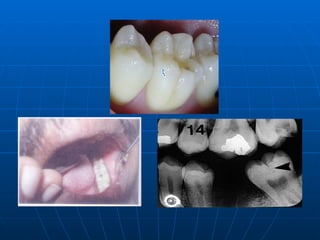

ROOT SURFACE CARIES The proximal root surface, particularly near the cervical line, often is unaffected by the action of hygiene procedures, such as flossing, because it may have  concave anatomic surface   contours (fluting)  and occasional roughness at the termination of the enamel. These conditions, when coupled with exposure to the oral environment (as a result of  gingival recession ), favor  the formation of mature, caries-producing plaque and proximal root-surface caries. Root-surface caries is more common in older patients. Caries originating on the root is alarming because    1. it has a comparatively  rapid progression    2. it  is often asymptomatic    3. it is closer to the pulp   4, it is more difficult to restore

The root surface is refer the enamel and readily allows plaque formation in the absence of good oral hygiene. The cementum covering the root surface is extremely thin and provides little resistance to caries attack. Root caries lesions have less well-defined margins, tend to be U-shaped in cross sections, and progress more rapidly because of the lack of protection from and enamel covering.

ROOT SURFACE CARIESThe proximal root surface, particularly near the cervical line, often is unaffected by the action of hygiene procedures, such as flossing, because it may have concave anatomic surface contours (fluting) and occasional roughness at the termination of the enamel. These conditions, when coupled with exposure to the oral environment (as a result of gingival recession ), favor the formation of mature, caries-producing plaque and proximal root-surface caries. Root-surface caries is more common in older patients. Caries originating on the root is alarming because 1. it has a comparatively rapid progression 2. it is often asymptomatic 3. it is closer to the pulp 4, it is more difficult to restore

The root surfaceis refer the enamel and readily allows plaque formation in the absence of good oral hygiene. The cementum covering the root surface is extremely thin and provides little resistance to caries attack. Root caries lesions have less well-defined margins, tend to be U-shaped in cross sections, and progress more rapidly because of the lack of protection from and enamel covering.